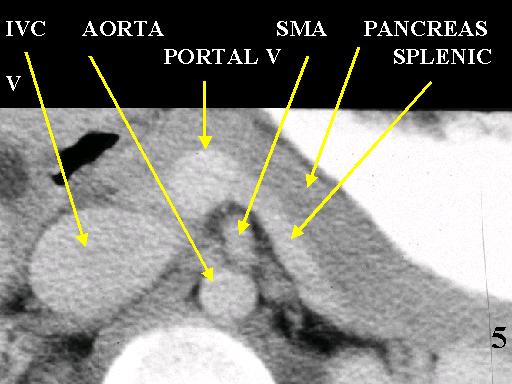

MS 190 CT 16